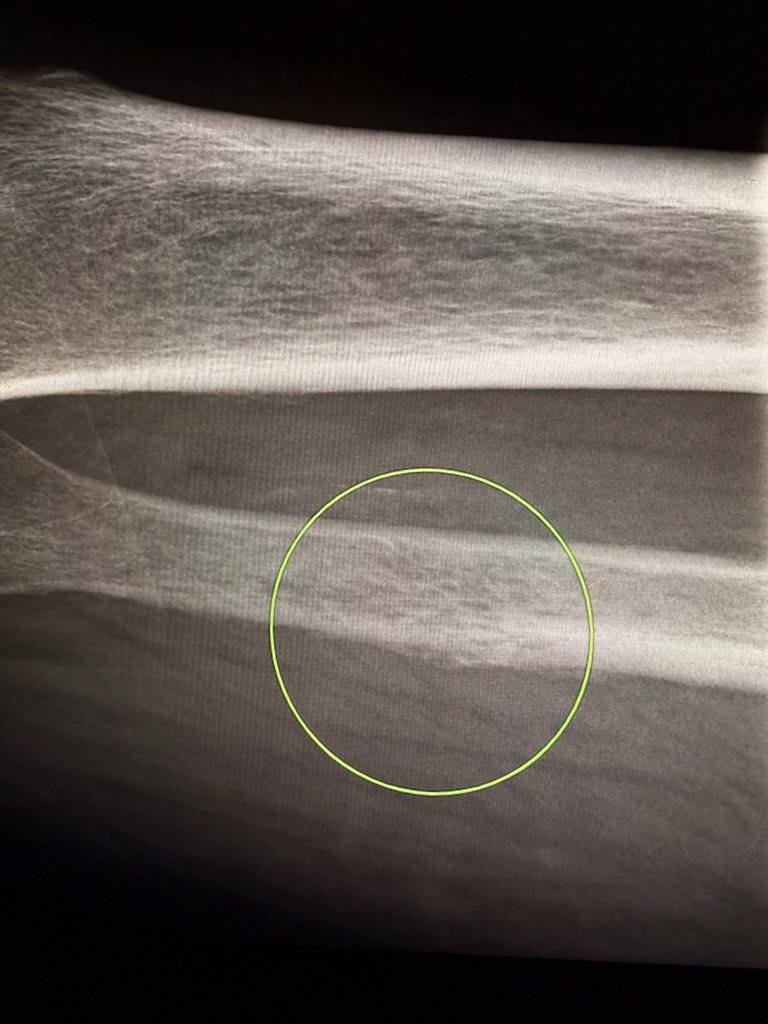

Osteoporosis can mimic an aggressive, permeative pattern on X-ray—especially in the pelvis, scapula, legs, and ribs. Don’t mistake it for malignancy or infection. Clue: Look for generalized demineralization and similar changes in the adjacent bones. —Pearls and pitfalls from

Osteoporosis can mimic an aggressive, permeative pattern on X-ray—especially in the pelvis, scapula, legs, and ribs.

Don’t mistake it for malignancy or infection.

Clue: Look for generalized demineralization and similar changes in the adjacent bones.